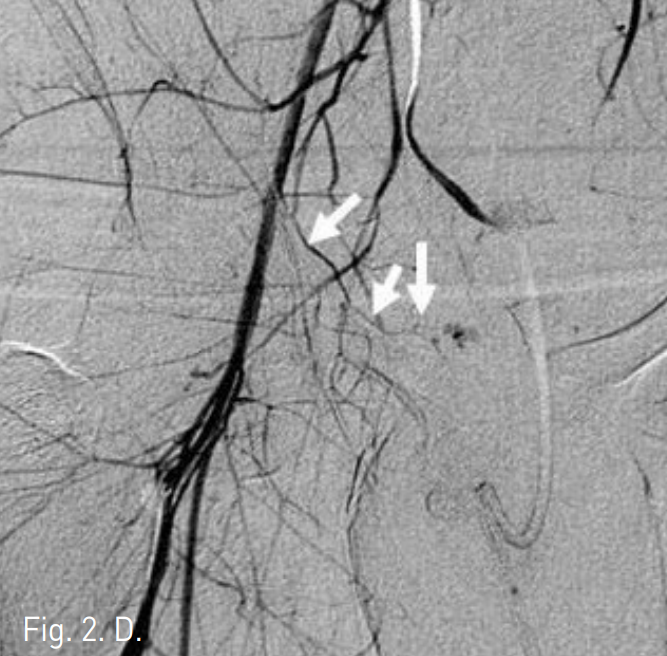

To identify the location of the bleeding site, digital subtraction angiography was performed. Selective angiogram of right common iliac artery showed two contrast extravasations or bleeding points at suprapubic area(Fig. 2A). Selective internal iliac arteriogram showed only one bleeding point from the obturator artery(Fig. 2B). After superselective cannulating into the feeding branch from the obturator artery by using a coaxial microcatheter, embolization was performed with gelfoam particles(Fig. 2C). Follow-up right common iliac angiogram showed persistent contrast extravasation and identified feeding branch of aberrant obturator artery from the inferior epigastric artery(Fig. 2D). Additional selective embolization was performed with gelfoam particles.

D. Persistent contrast extravasation being fed by aberrant obturator artery (arrows), a branch of inferior epigastric artery, is identified on common iliac angiogram. So additional selective bleeding artery embolization was done.